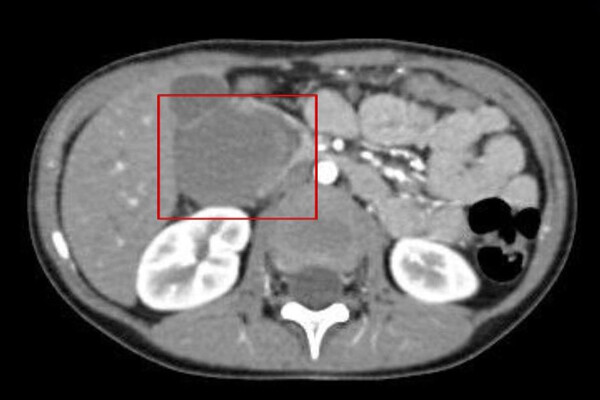

«Причиной кишечной непроходимости стала травма живота: после падения на подлокотник дивана у ребенка выросла гематома 52 мм на 48,5 мм», — пояснили в пресс-службе ведомства.

Пациенту провели лапароскопическую операцию. Во время нее хирурги обнаружили, что гематома образовалась между двумя слоями двенадцатиперстной кишки и, по их словам, «чудом ее не повредила». Специалисты добрались до гематомы и вскрыли ее.